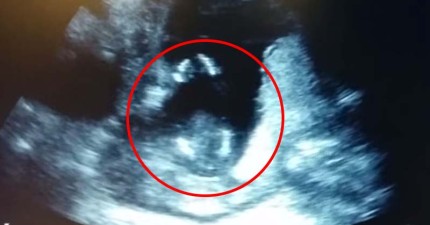

這個還在肚中的寶寶,竟然在超音波檢查時跟爸媽超溫馨一拍一唱!

March 28, 2015

世界